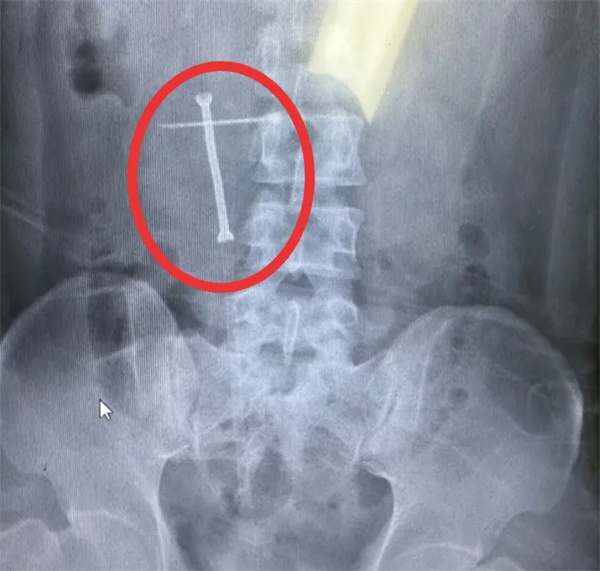

通過(guò)術(shù)中X線結(jié)合輸尿管鏡檢查,醫(yī)生精準(zhǔn)定位該患者的輸尿管狹窄段長(zhǎng)度和位置,利用支架附帶的導(dǎo)入系統(tǒng)精準(zhǔn)地將支架放置到預(yù)定位置。隨后注入熱水,鎳鈦合金支架雙端膨脹,成功地固定在患者輸尿管狹窄位置,將狹窄段撐開(kāi)為患者提供尿液引流效果,讓輸尿管狹窄段重新恢復(fù)通暢。

(置入支架后,輸尿管狹窄段重新恢復(fù)通暢)